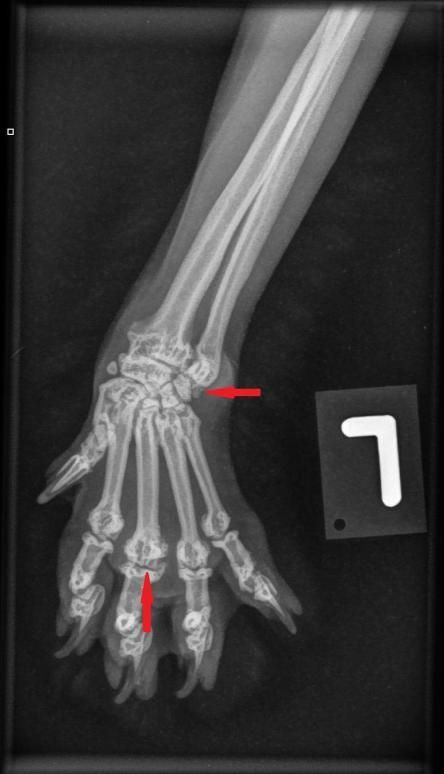

Die Besitzerin berichtet, dass der Kater recht lahmheitsfrei laufe, aber nicht über eine grosse Sprungkraft verfüge. Die Beine von Maxwell sind eher kurz und er scheint hinten und vorne X-beinig. Der Gang der Katze wirkt staksig; eine eigentliche Lahmheit ist nicht zu sehen. Um Aufschluss über die Situation in den Gelenken zu erhalten, werden die Vorderpfoten/Handgelenke, Hinterpfoten/Fusswurzelgelenke und die Wirbelsäule geröntgt. Es ist zu erkennen, dass Hand- und Fusswurzelgelenke gegenüber der Normalsituation eine X-beinigkeit (Valgisierung) aufweisen, an verschiedenen Stellen Anzeichen einer Arthrose vorhanden sind und insbesondere die Mittelhand- und Mittelfussknochen kurz und gedrungen erscheinen. Ein Teil der Fusswurzelknochen von Maxwell sind ausserdem zu einem einzigen Knochen verwachsen.

Vorderpfote links Maxwell Vorderpfote links normale Katze